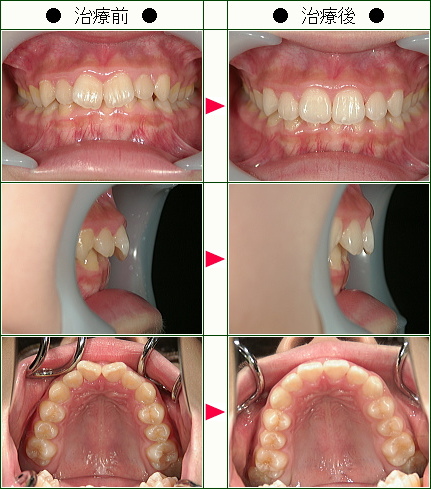

歯のデコボコ矯正の治療症例解説<上だけの症例>(19歳以下)--部分矯正--その4

☆歯のデコボコ矯正症例[N.A様 14歳 女性]